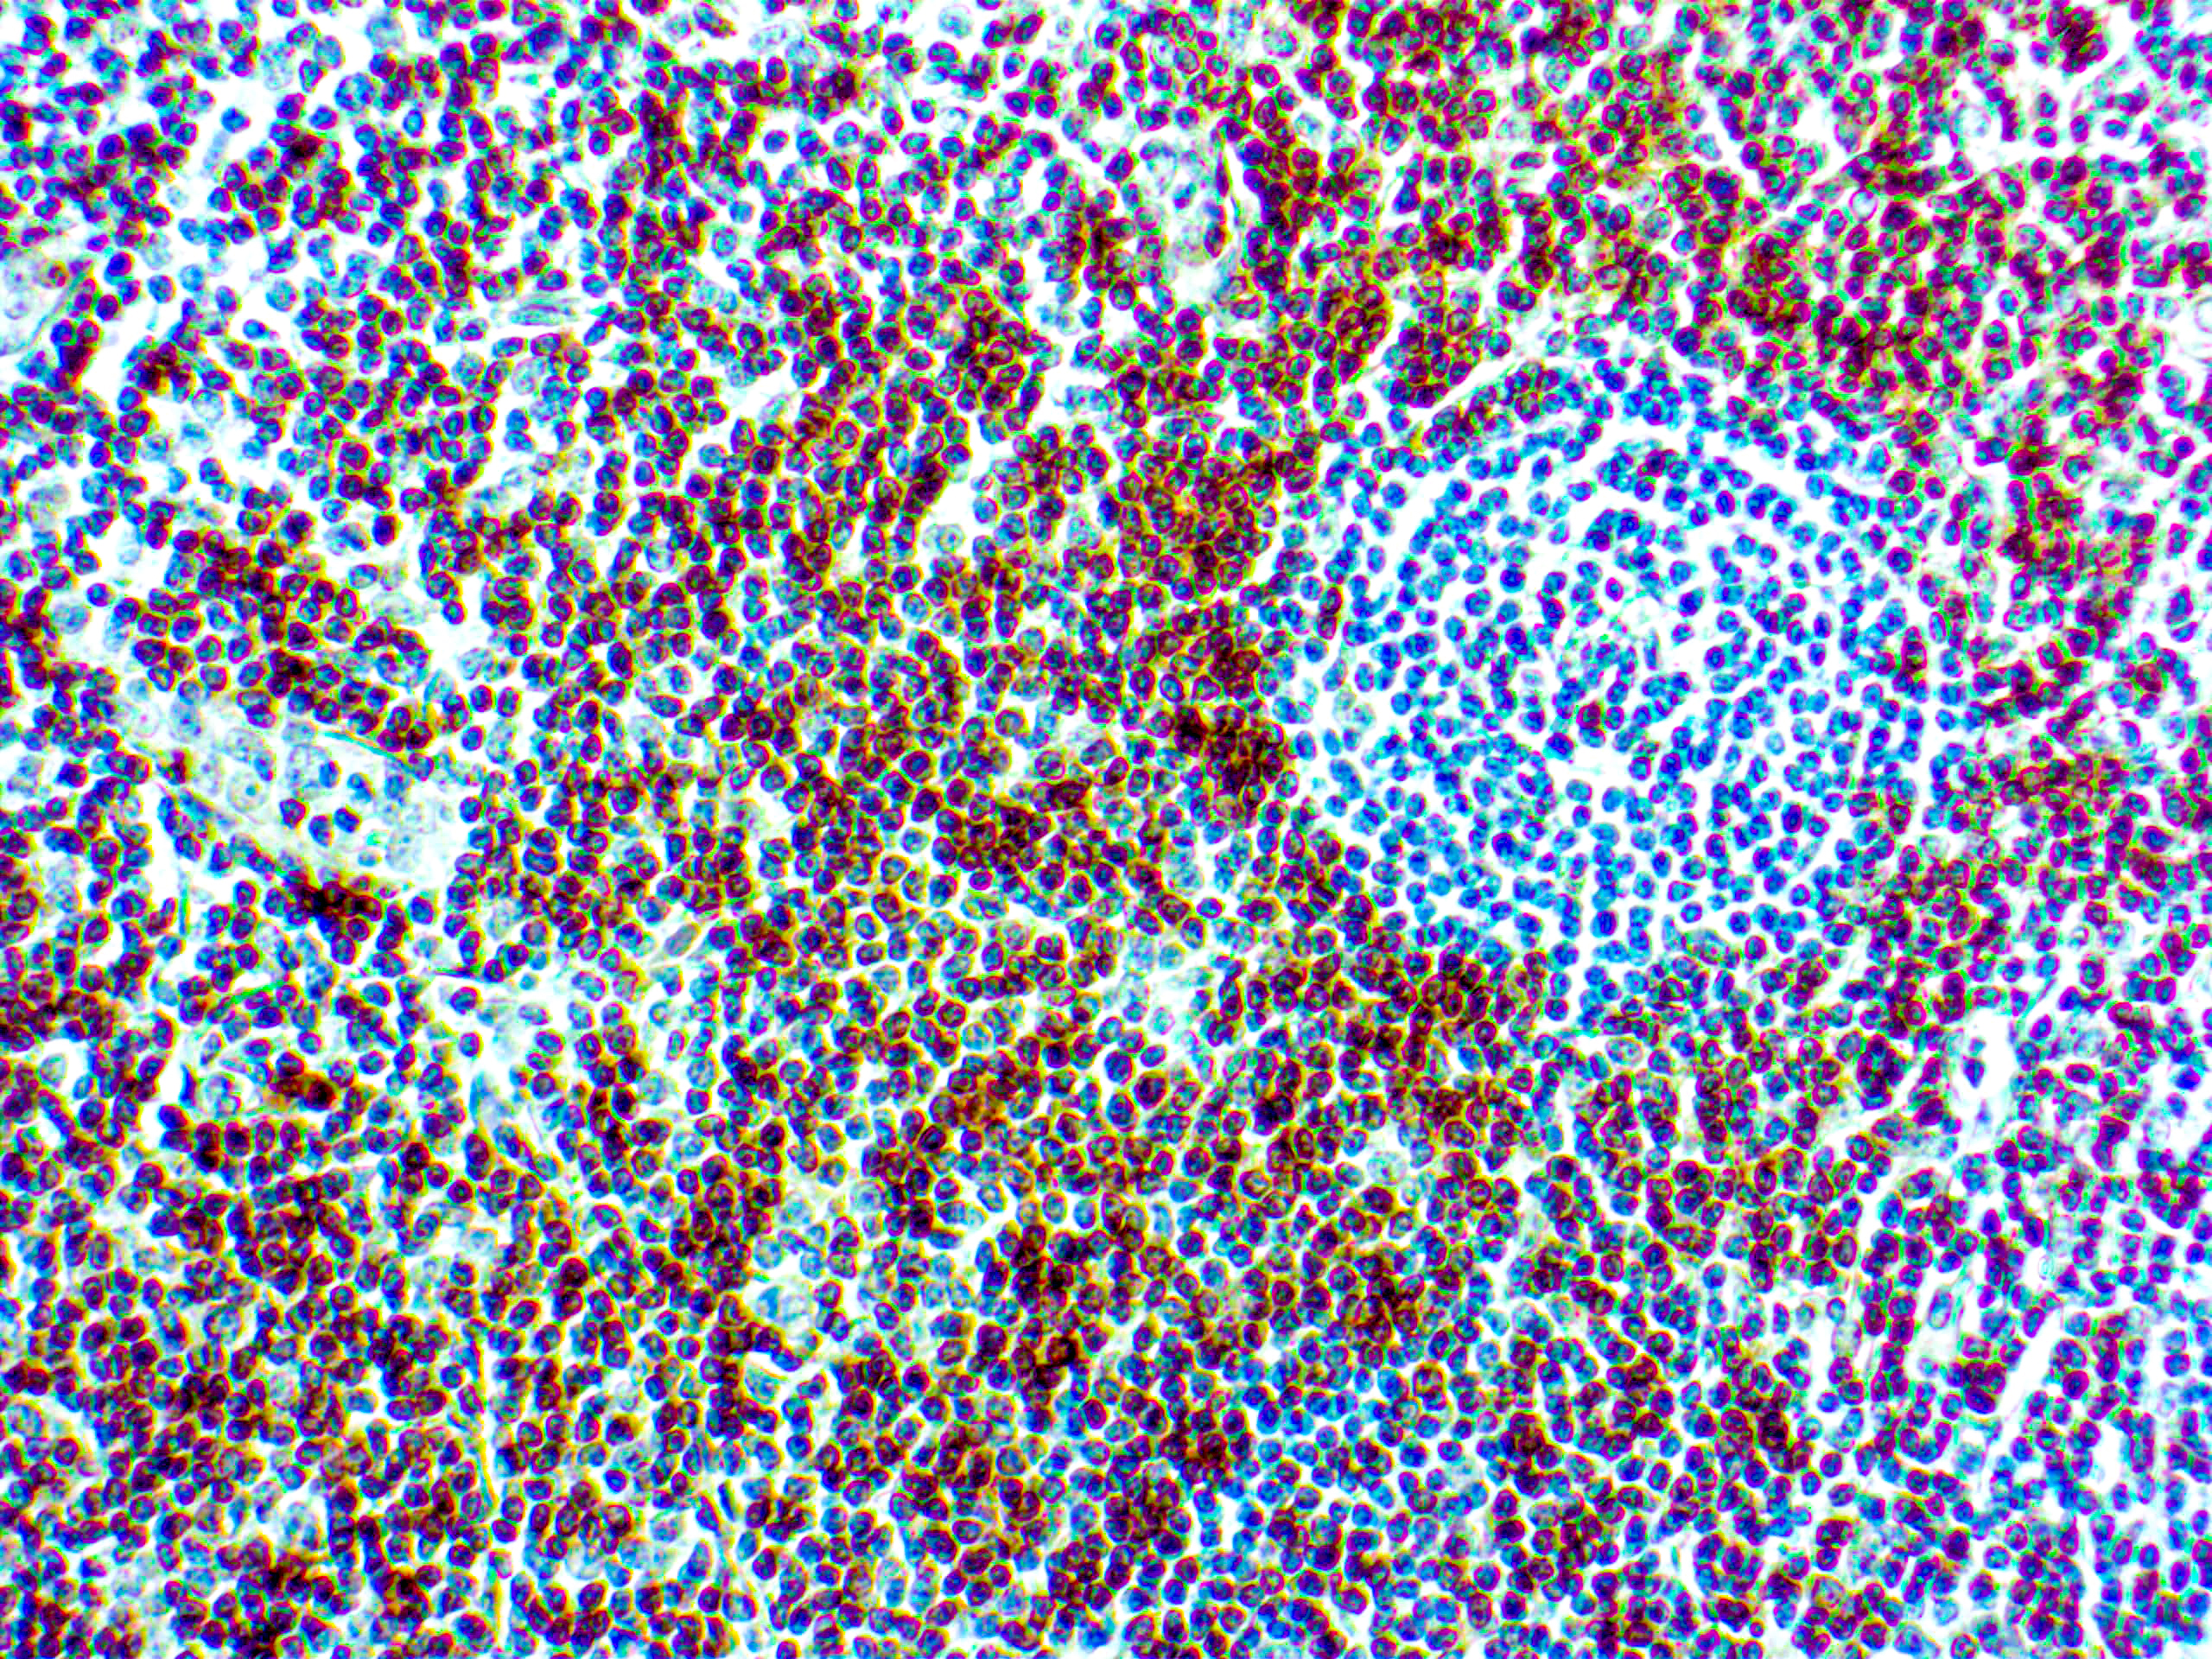

CD7 is expressed by most peripheral blood T cells, NK cells, and all thymocytes. It is one of the earliest surface antigens on T and NK-cell lineages. The antibody is a useful aid for classification of T-cell malignancies.

| Positive Control Tissue | Tonsil |